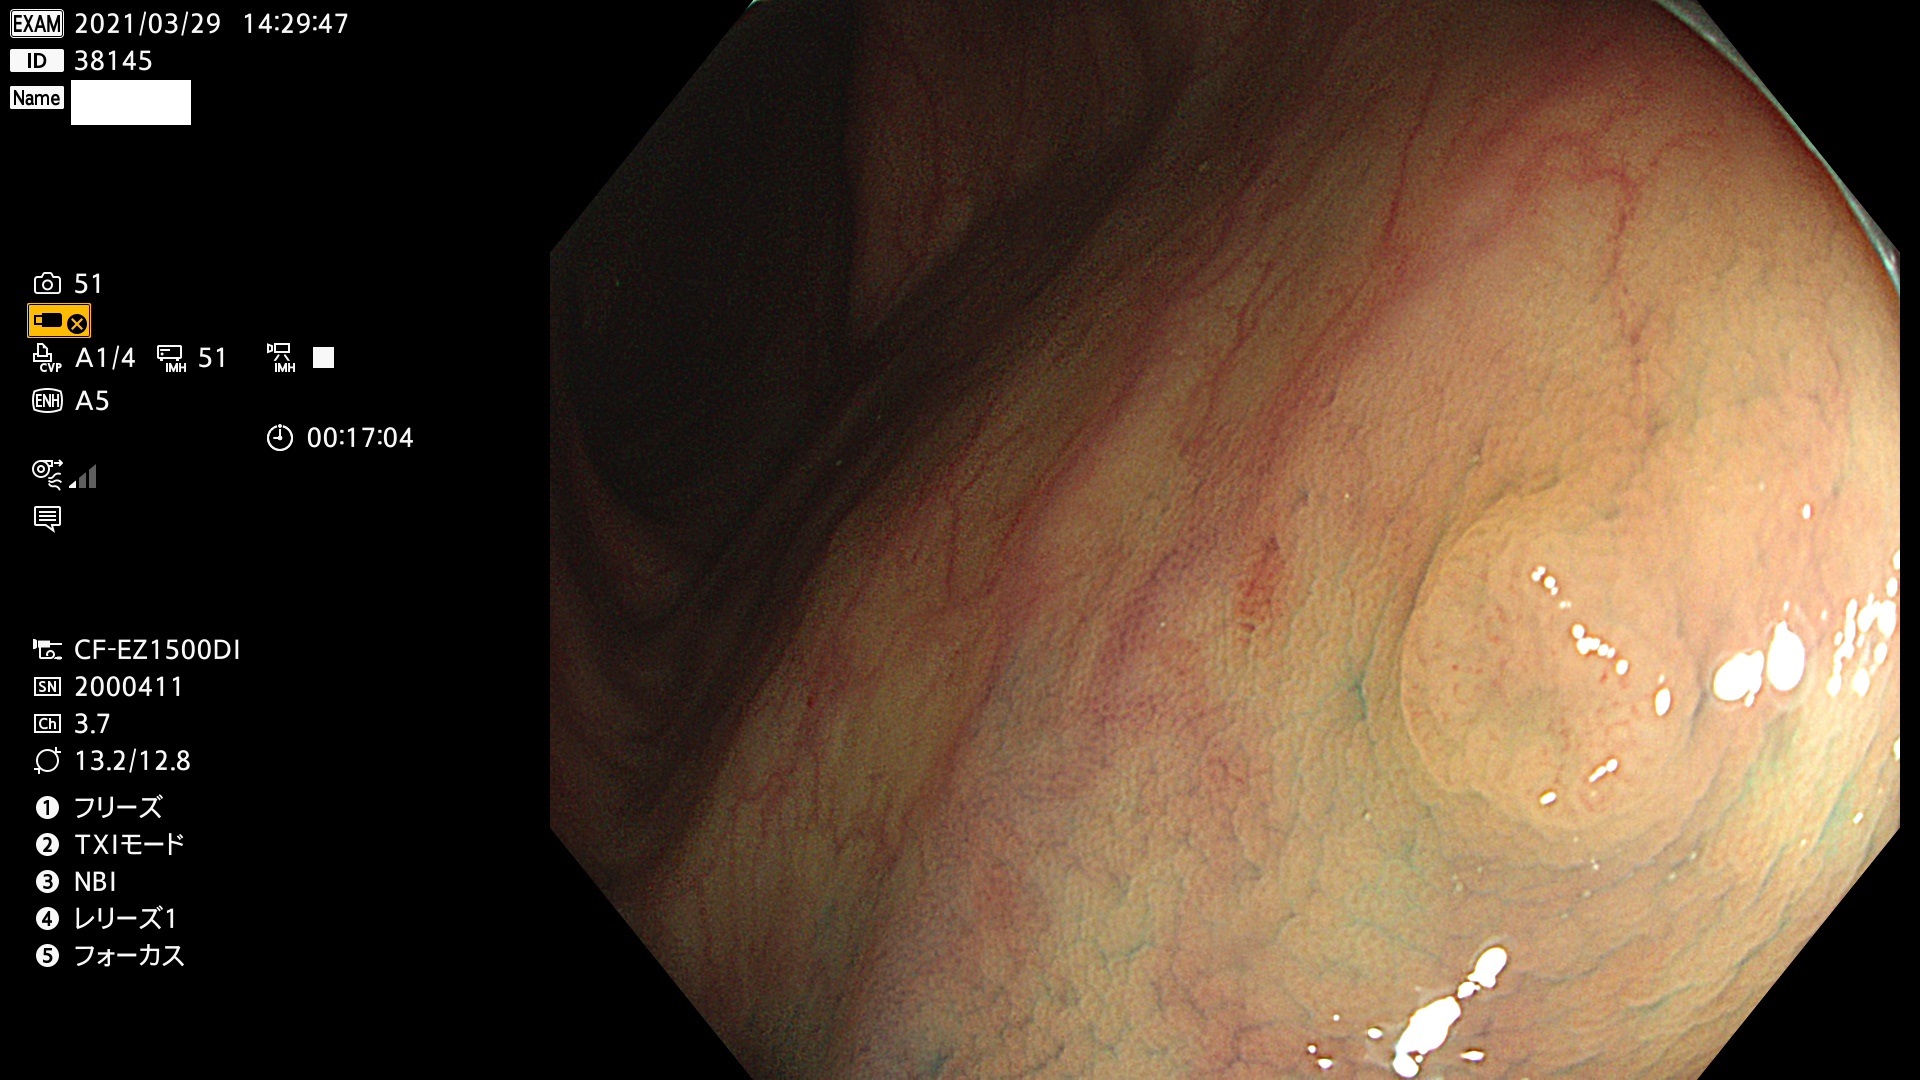

腺腫発見率 72 % (カルテ番号 38100〜38199の100名の方の検査結果で集計)大腸癌検診最新情報

以下のカルテ番号の方に腺腫(Adenoma,Group3〜5)が見つかりました(集計法)

38101 38103 38104 38106 38107 38108 38109 38110 38111 38112 38113 38114 38115 38117 38118 38122 38123 38124 38125 38126 38127 38128 38130 38131 38132 38135 38137 38138 38140 38141 38142(SSAPのみ) 38143 38144 38145 38146 38147 38148 38149 38150 38151 38152 38153 38154 38157 38158 38160 38161 38162 38164 38165 38166 38167 38168 38169 38172 38176 38177 38178 38181 38182 38183 38184 38187 38189 38190 38191 38192 38193 38194 38195 38196(SSAPのみ) 38198

発見困難で危険性の高い平坦型病変(上記100名より抽出) ![]()